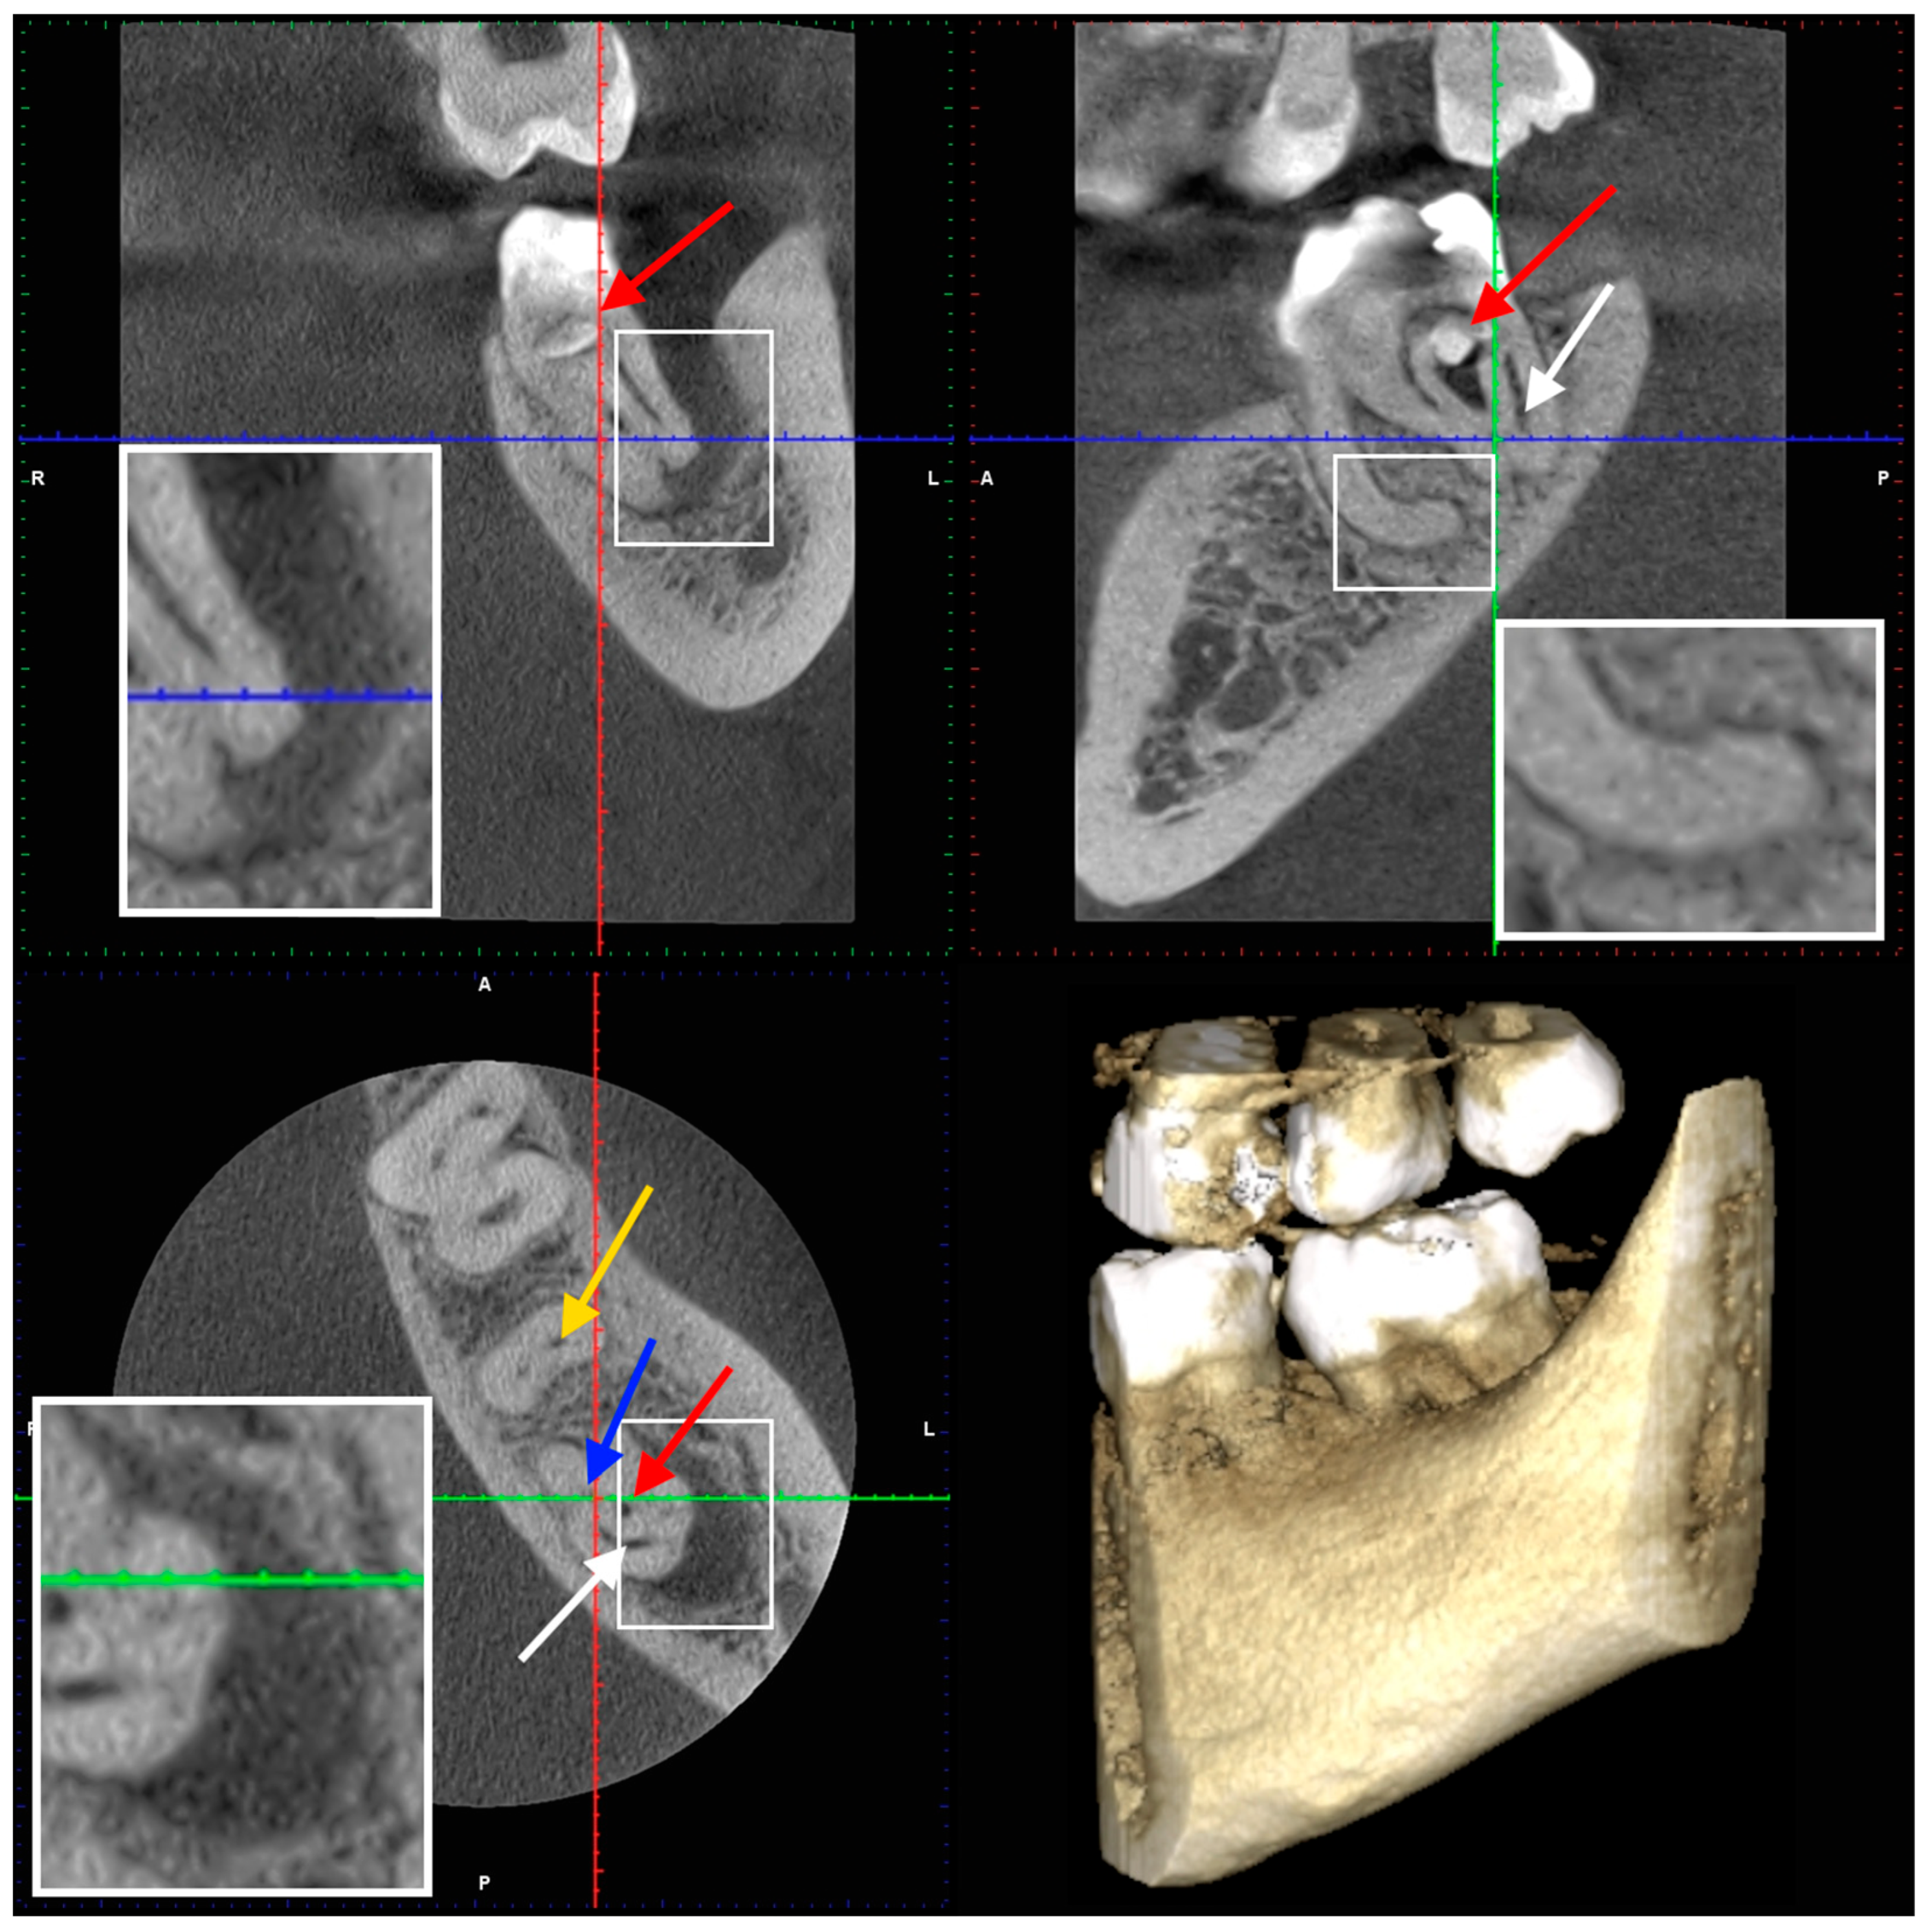

2. Case Presentation

2.1. The First Visit